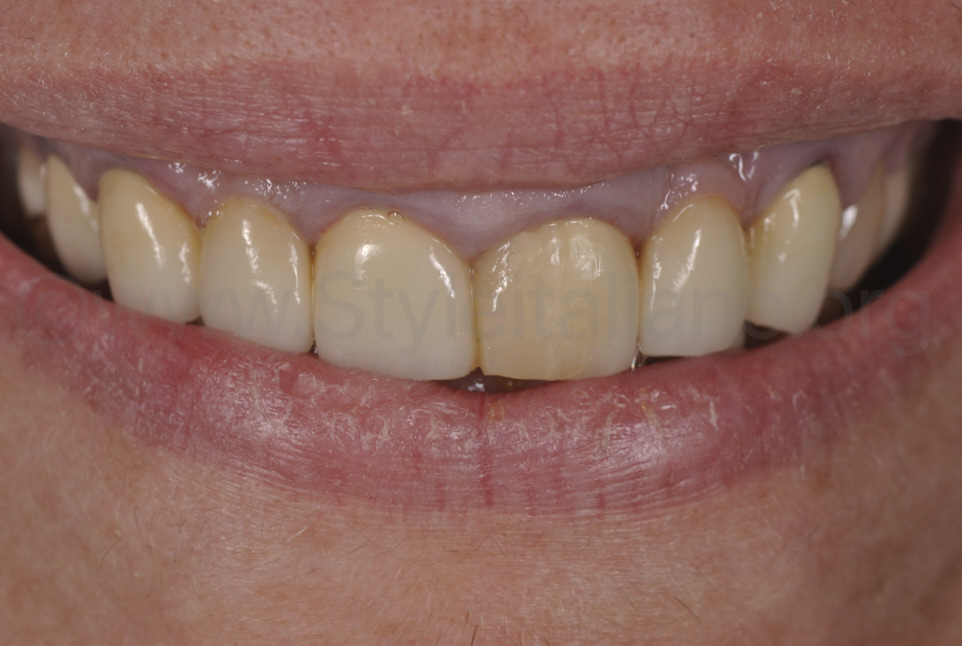

Фото 15.

Вигляд збоку, з ідеальним ясенним профілем. Процес загоєння проходив відповідно до форми країв керамічної реставрації.

Фото 16.

Вигляд з іншого боку, з ідеальним ясенним профілем і таким самим зубоясенним переходом.